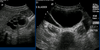

How is testicular torsion diagnosed?

Ultrasound (see lack of blood flow) is definitive but not mandatory if:

Describe diagnosis of epididymo-orchitis, epididymitis, and orchitis

- Imaging with scrotal ultrasound

- Enlarged, hypervascular epididymis

- Normal or increased testicular blood flow